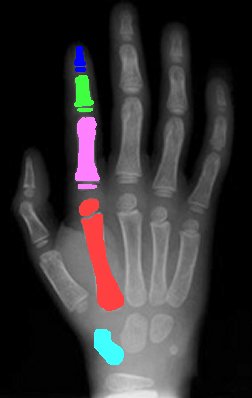

in image

Click

on area of interest

Use

index finger for phalanges

Middle finger for joints

(Coloured areas have information.)

Anatomy

Most fractures

of the hand in children involve the growth plate in the zone of hypertrophy.

NB growth plates exist only in the proximal end of phalanges, the proximal end

of the thumb metacarpal, and the distal end of the finger metacarpals.

Anomalies do

exist, and an epiphysis or pseudoepiphysis must be ruled out when considering

fractures in the paediatric hand.